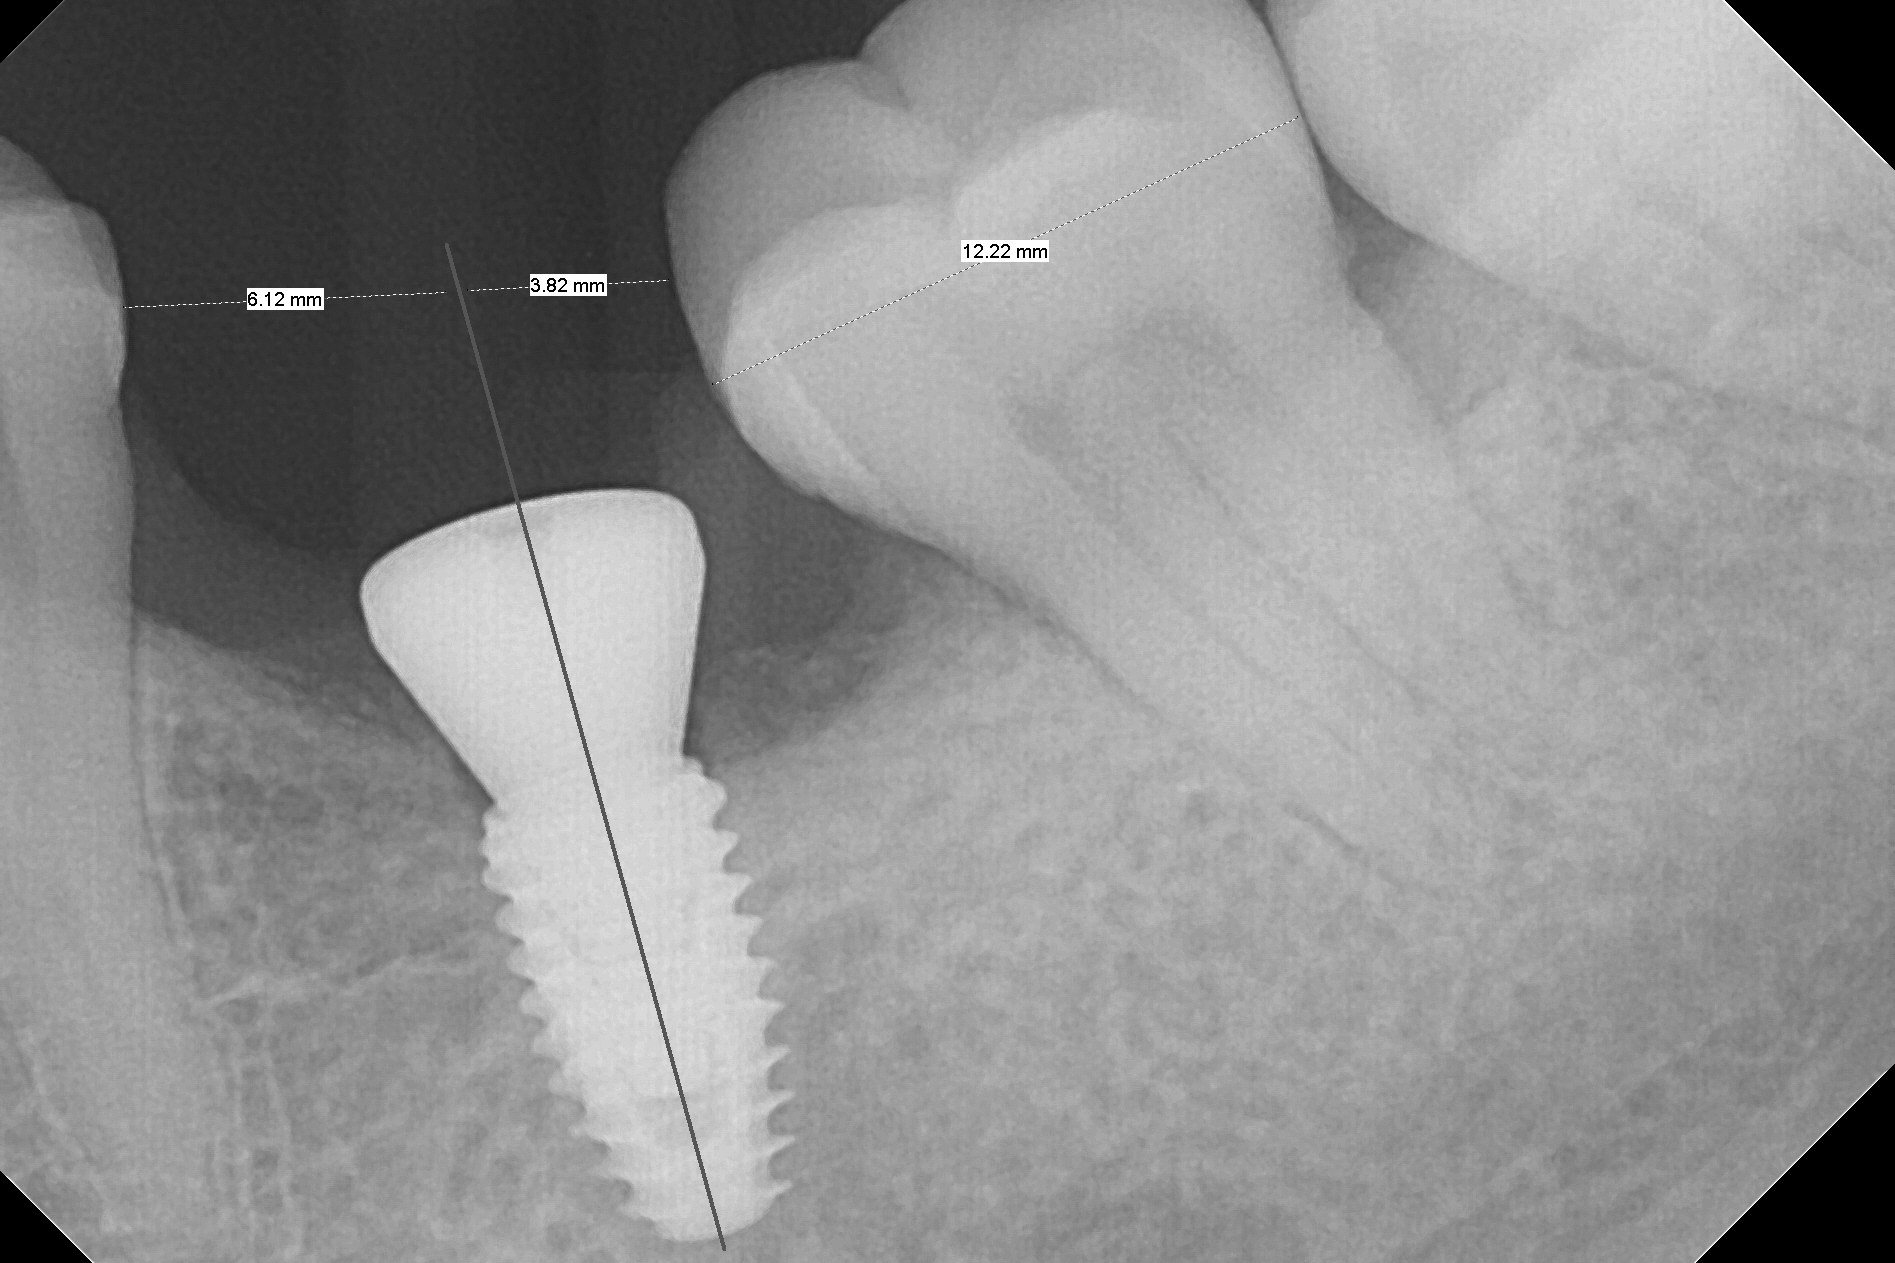

With 34 mg of Lidocaine and 17 mcg of Epinephrine (local infiltration), a 4.5x8.5 mm implant is placed with guide. The insertion torque is ~50 Ncm. It is placed in precise depth and in a short period of time (tolerable to the operators and patient, easier than mini-implant placement, Fig.1). There is no postop pain or paresthesia. The mesidistal position is within treatment plan (Fig.2). Miniimplants are placed to intrude #14 14 days prior. The teeth #16,17 and 32 are extracted 3 months postop. Minimal bone resorption at the crest is noted nearly 4 months postop (Fig.3). Bands and brackets are placed #18 upright 4 months postop (Fig.4 (14 niti wire)). The buccal and lingual view of the preop model shows that the supraerupted 1st molar (#14) has close relationship with the distal surface of the tooth #20 (Fig.5,6), accounting for the severe wear of the latter (Fig.8-11). The implant not only acts as an anchor to upright #18 in 4.5 months post banding (Fig.7 *), but also as an occlusal stop so that #18 has no interference to be moved. The stress on the implant results in radiating trabecular pattern (Fig.7,11 (9,11 months postop), as compared to before loading (Fig.1,3)). Restoring the distal contour of #20 with composite (Fig.12 C) makes it easy to close the space by adding porcelain the mesial surface of the implant crown. The crown/abutment is loose in China 7 months post cementation.